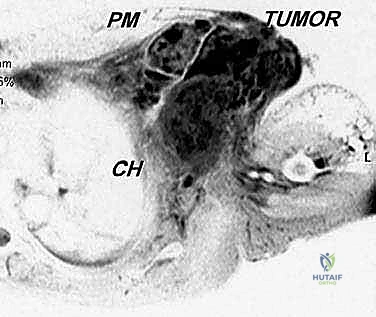

في حالة الأورام الخبيثة (مثل الساركوما)، يمتد الورم غالبًا عبر الحواجز العضلية ويغزو الضفيرة العضدية (شبكة الأعصاب التي تغذي الذراع) والأوعية الدموية تحت الترقوة. لضمان عدم ترك أي خلايا سرطانية (تحقيق هوامش جراحية سلبية)، يجب إزالة الكتف بالكامل كوحدة واحدة (En Bloc resection).

- ساركوما العظام (Osteosarcoma & Ewing's Sarcoma): أورام عظمية خبيثة تنشأ في الطرف العلوي لعظمة العضد أو لوح الكتف وتكون قد وصلت لمرحلة متقدمة لا تستجيب للعلاج الكيميائي.

- ساركوما الأنسجة الرخوة (Soft Tissue Sarcoma): أورام ضخمة تنشأ في العضلات أو الأنسجة المحيطة بالكتف وتغزو الأوعية الدموية الرئيسية والأعصاب.

- التصوير الطبي المتقدم: استخدام الرنين المغناطيسي (MRI) لتقييم الأنسجة الرخوة، والأشعة المقطعية (CT scan) للصدر للبحث عن أي نقائل سرطانية (Metastasis)، والتصوير المقطعي بالإصدار البوزيتروني (PET Scan).